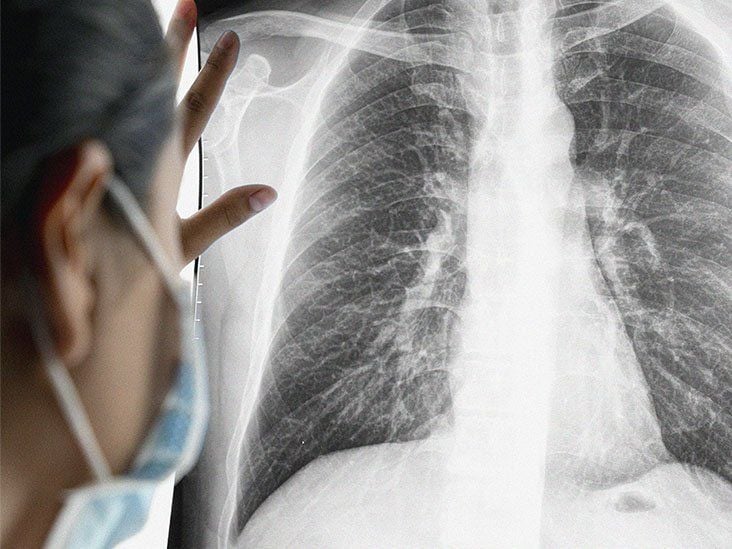

Sau khi tìm hiểu, bác sĩ phát hiện nguyên nhân chính gây nên bi kịch này là do người chồng trước đó là người hút thuốc lá rất nặng, thường xuyên hút ngay trong nhà. Điều này khiến cả gia đình tiếp xúc với khói thuốc thụ động, dẫn đến nguy cơ mắc ung thư phổi rất cao.

Theo Healthline, trong khói thuốc lá có hơn 7.000 chất hóa học, ít nhất 70 chất đã được chứng minh gây ung thư (carcinogens) như: Benzene, formaldehyde, arsenic, cadmium… Các chất này khi xâm nhập vào phổi sẽ phá hủy tế bào, biến đổi ADN, dẫn đến sự hình thành và phát triển của tế bào ung thư.

Hút thuốc khiến niêm mạc phổi bị kích ứng và viêm mãn tính, cản trở quá trình tự phục hồi, gây đột biến gen trong tế bào phổi. Việc hút nhiều điếu mỗi ngày trong nhiều năm khiến phổi bị "ngâm" trong chất độc liên tục, làm tăng nguy cơ ung thư cao hơn nhiều lần so với người không hút.

Người không hút nhưng hít phải khói thuốc cũng tiếp nhận gần như đầy đủ các chất gây ung thư. Đặc biệt nguy hiểm với phụ nữ, trẻ em, người già sống chung với người hút thuốc.